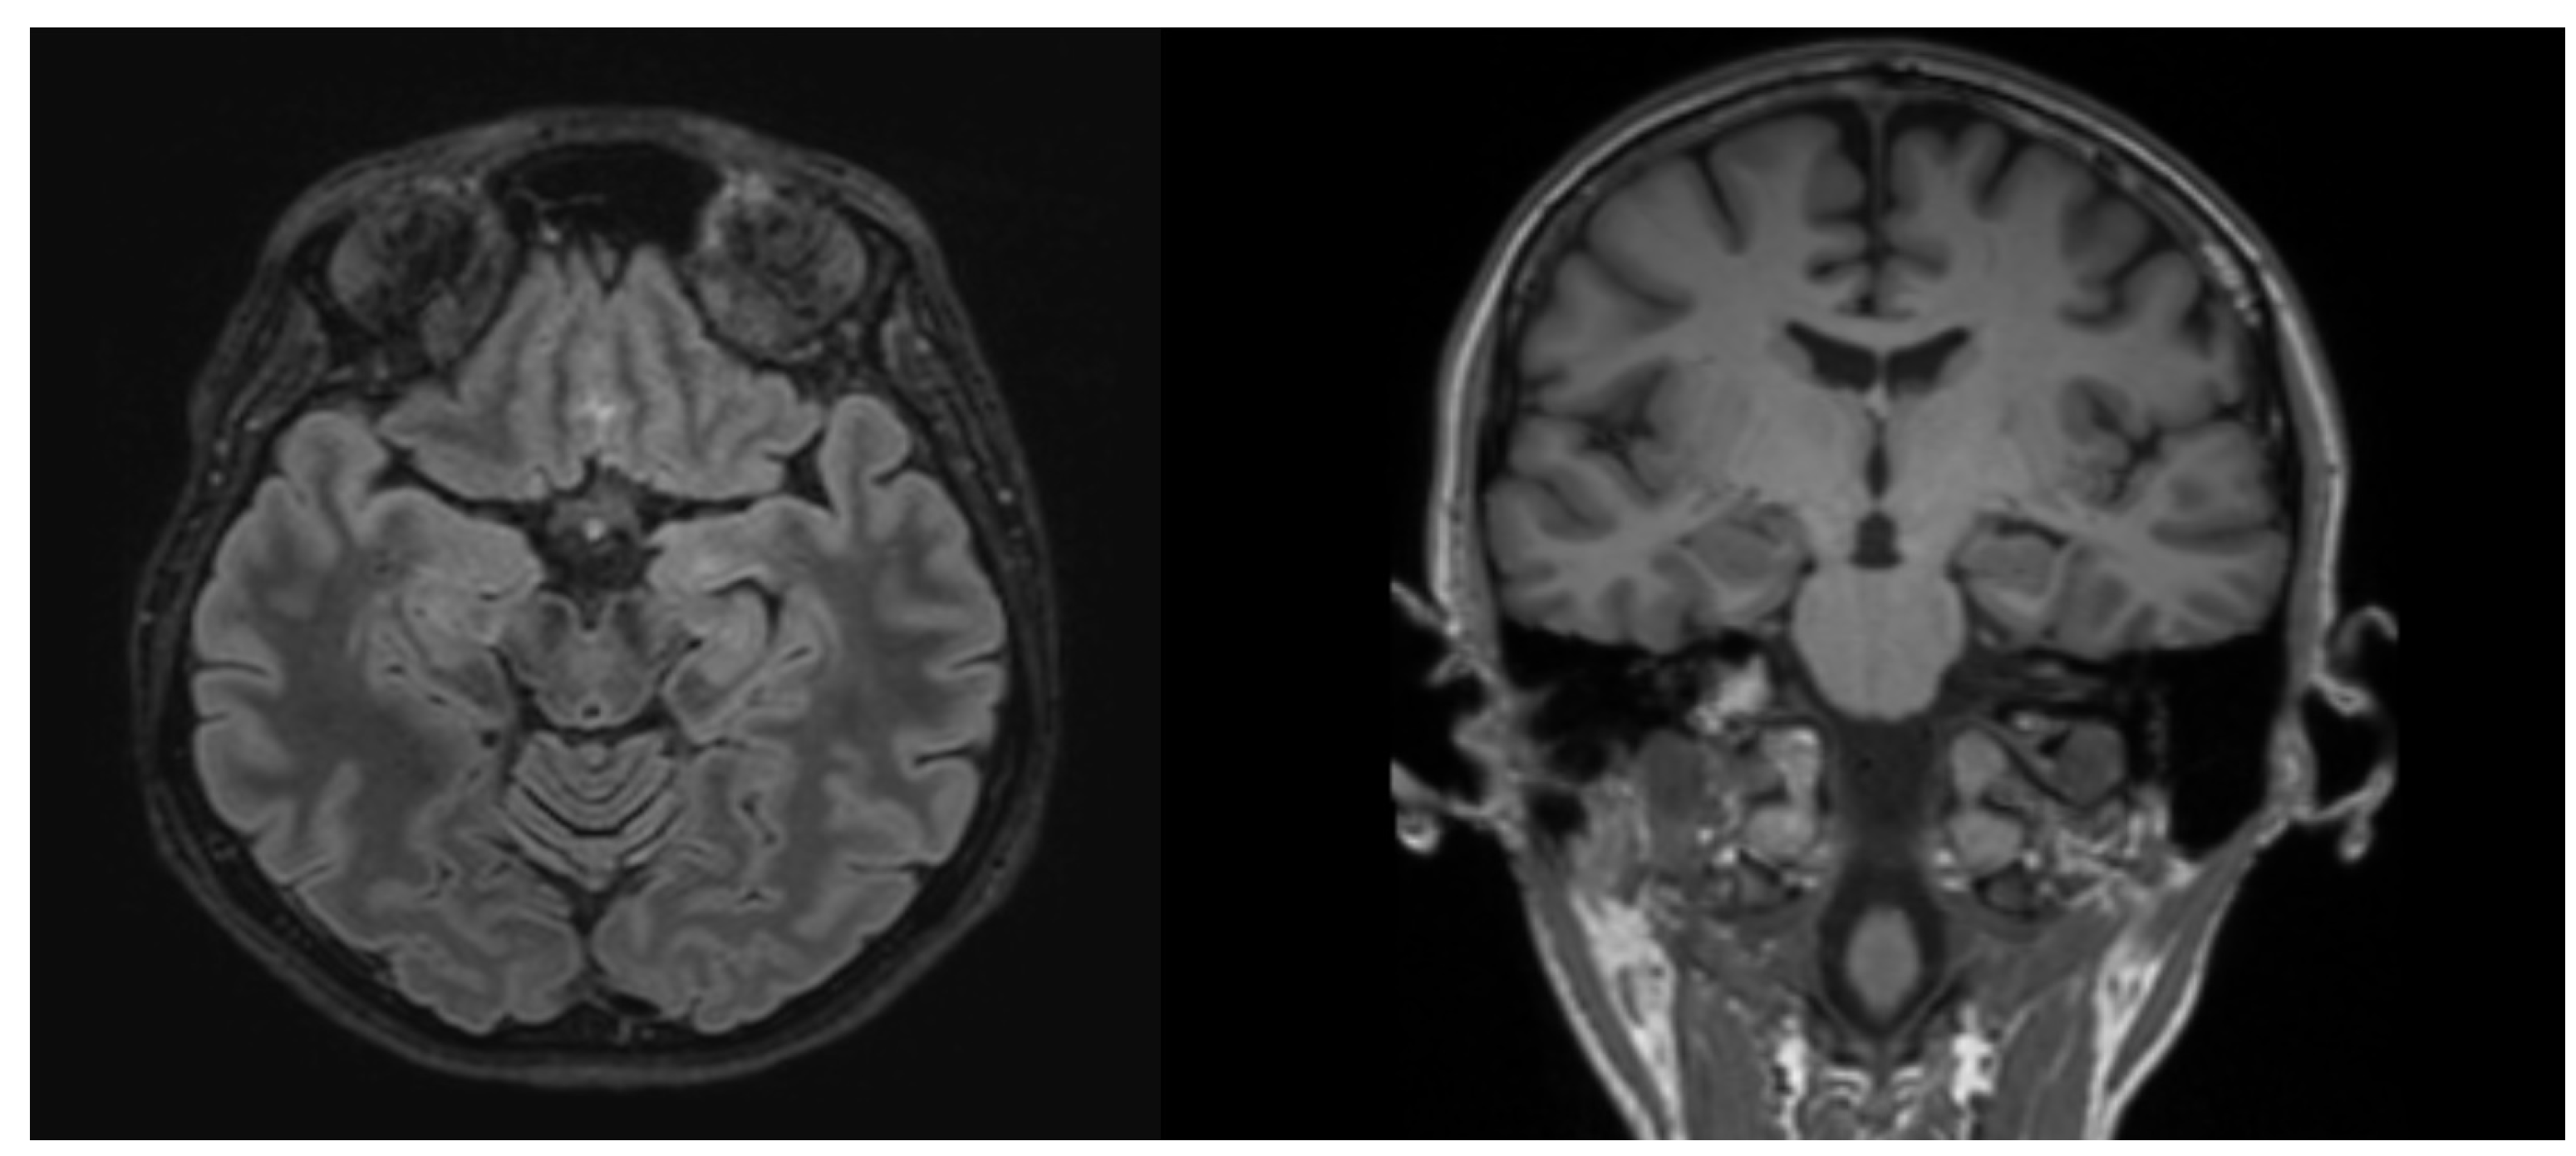

2. Case Report

| Clinical presentation | Very variable and includes combinations of seizures, prominent psychiatric manifestations, sleep and movement disorders, memory impairment, and autonomic instability. MRI is often abnormal. | There are no other neurological signs and drug-resistant epilepsy is most frequently the only clinical feature. MRI is usually unremarkable. |